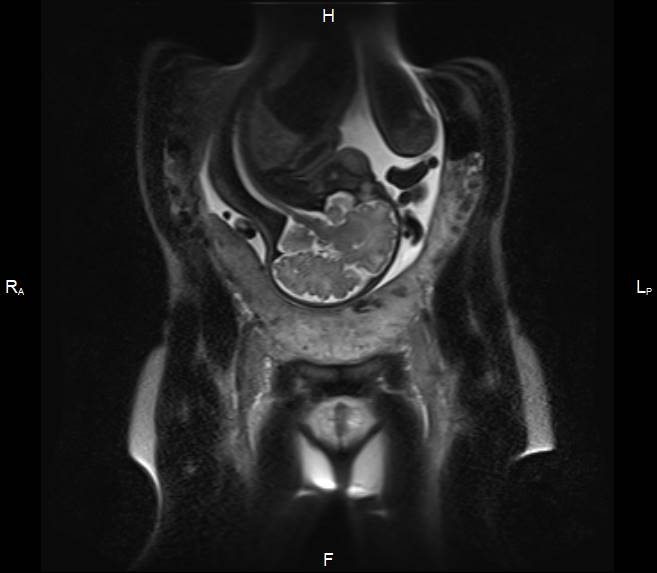

Первичный, или «материнский» этап, длительностью 3–5 минут, при котором получаемые Т2-ВИ многоплоскостные ортогональные МР-изображения (рисунок 1) ориентируются согласно анатомии беременной; целью его является оценка сегментарного расположения плацентарного диска в полости матки, контуров и размеров матки.

| Рисунок 1 – Беременность 36 нед. МРТ плаценты. Первичный, «материнский» этап исследования. Т2 ВИ в сагиттальной (а), корональной (б) и аксиальной (в) плоскостях | ||